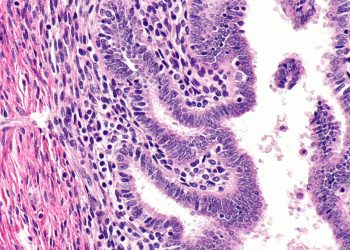

Causes and Risk Factors of Adenomyosis

Causes and Risk Factors of Adenomyosis The exact...